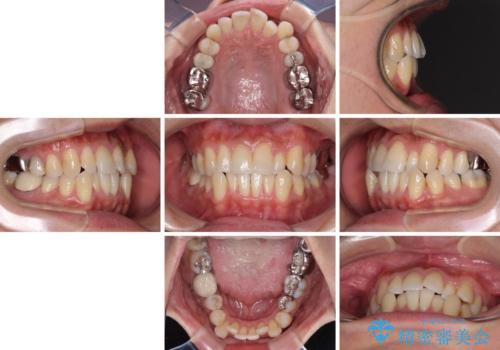

受け口傾向の咬み合わせ 前歯のデコボコをワイヤー矯正で素早く改善

前歯のクロスバイトは、改善の途中で歯髄壊死を起こすリスクが高くなるため、マウスピース矯正よりもワイヤー矯正をお勧めしております。

この患者様もクロスバイトはあっという間に改善され、1年強で速やかに治療を終えることができました。